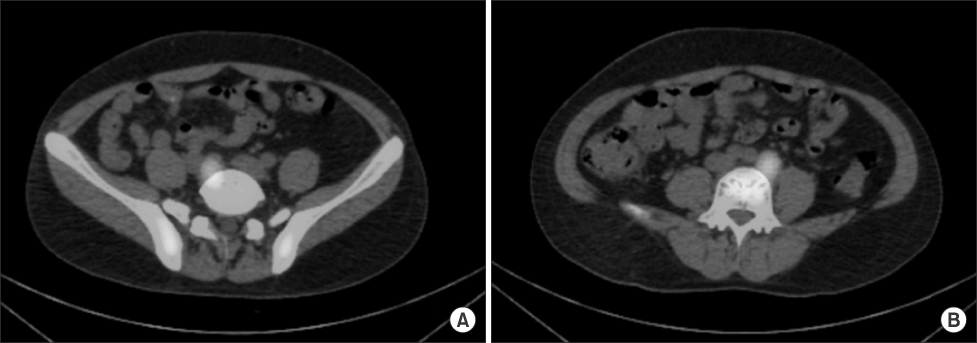

Fig. 2

Technetium-99m RBC scintigraphy shows uptake in both common iliac area masses. (A) Right side. (B) Left side.

Fig. 2 Technetium-99m RBC scintigraphy shows uptake in both common iliac area masses. (A) Right side. (B) Left side.